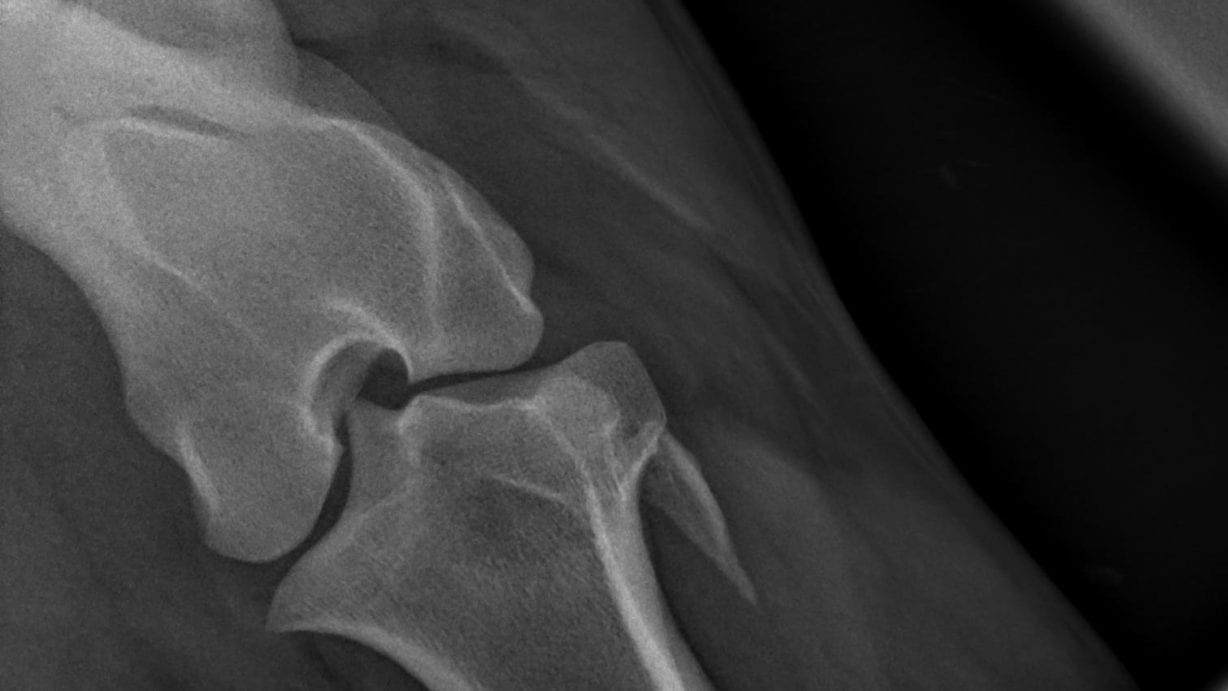

Voor een juiste beeldvorming wordt veelal het röntgenapparaat toegepast. Door middel van röntgenstralen worden foto’s gemaakt van de binnenkant van het lichaam. Op deze manier kan het skelet van het paard, maar organen goed in beeld worden gebracht.

We gebruiken het röntgenapparaat vaak in de orthopedie, wat zich bezighoudt met het onderzoek en behandeling van het bewegingsapparaat. Kreupelheid, fracturen, standsafwijkingen en botontstekingen worden door middel van röntgenonderzoek in beeld gebracht. Daarnaast kunnen we ook aanhechtingsproblemen van pezen en banden, maar ook botafwijkingen zien.